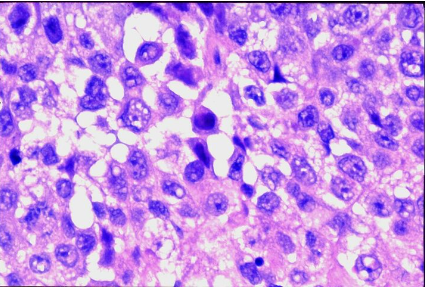

The diagnosis is _____ carcinoma of the lung.